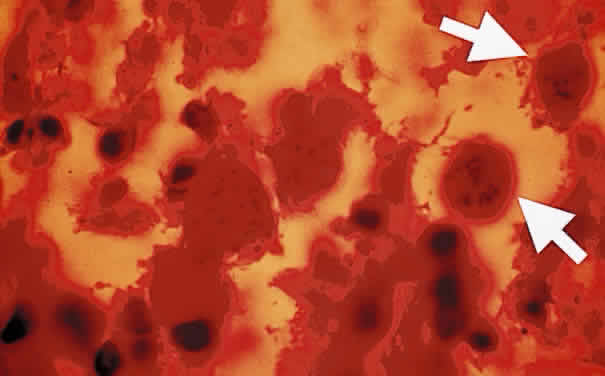

Fig. 1. Toxoplasma gondii. Tachyzoites from the peritoneal exudates of infected mice stained with Giemsa (× 100).

Tachyzoite is the proliferative form of the organism, which used to be known as trophozoite. It has a crescent shape and measures approximately 7 μm in length and 3 μm in width (Fig. 1). The organism is motile with a unique cytoskeletal structure allowing it to twist, wiggle, rotate, and glide. The rostrum of the tachyzoite is known as the conoid, which can extend, retract, tilt, and rotate. These movements allow the tachyzoite to find its target host cell and to penetrate the cell, establishing an intracellular existence. Tachyzoites are easily propagated in peritoneal cavities of mice and in mammalian tissue culture cell lines. The organism has the ability to replicate in all mammalian nucleated cells. In the host cell, the tachyzoite multiplies by endodyogeny; this reproductive process is susceptible to heat, freezing and thawing, desiccation, and gastric enzymes.